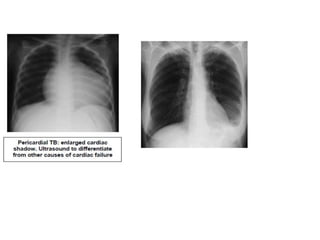

Radiological diagnosis

Chest X-ray

CXR remains an important tool for diagnosis of PTB in children who are sputum smear

negative or who cannot produce sputum

• Pleural or pericardial effusion – though seen on CXR – are forms of extra

pulmonary TB that tend to occur in older children

Radiological diagnosis Chest X-ray CXRremains an important tool for diagnosis of PTB in children who are sputum smear negative or who cannot produce sputum The following abnormalities on CXR are suggestive of Tb :- • Enlarged hilar lymph nodes and opacification in the lung tissue. • Miliary mottling in lung tissue • Cavitation (tends to occur in older children) • Pleural or pericardial effusion – though seen on CXR – are forms of extra pulmonary TB that tend to occur in older children • The finding of marked abnormality on CXR in a child with no signs of respiratory distress (no fast breathing or chest indrawing) is supportive of TB

Primary Tuberculosis onCXR 1.GangliopulmonaryTB ( Characterized by the presence of mediastinal and/ or hilar lymphadenopathy and parenchymal abnormalities, the Ghonfocus 2.TuberculousPleuritis 3.MiliaryTB 4.Tracheobronchial TB

• Computed tomography(CT) scan of the chest may be used to further delineate the anatomy for cases in which radiographic findings are equivocal. Endobronchial involvement, bronchiectasis, and cavitations may be more readily visualized on CT scans than chest radiographs . However, there is no role for routine use of CT scans in the evaluation of an asymptomatic child since treatment regimens are based on chest radiography findings . • In the setting of tuberculous meningitis, CT scan of the head is useful. Hydrocephalus and basilar meningeal enhancement are observed in 80 and 90 percent of cases, respectively; chest radiography may be normal. Abdominal u/s findings on TB : - Abdominal lymph node enlargement - Splenic lesions and ascites -